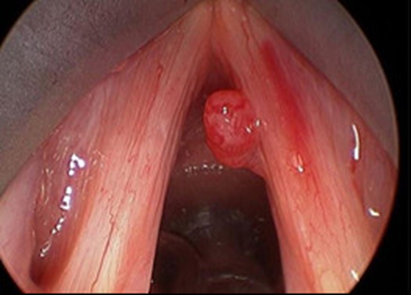

1.1 Papiloma thanh quản (hay còn gọi là u nhú thanh quản) là một thương tổn lành tính ở thanh quản và khí quản. Bệnh u nhú thanh quản có thể gặp ở người lớn và trẻ em với diễn tiến lâm sàng có hơi khác nhau.

- Nguyên nhân gây bệnh: Chưa rõ ràng. Thuyết về nguồn gốc siêu vi: được chú ý nhiều nhất. Nguyên nhân được cho là do Papilloma virus gây bệnh ở người HPV (Human papilloma virus) typ 6 và 11.

- Giải phẫu bệnh: Đại thể: là những khối sùi hình quả dâu tằm, hoặc hình súp-lơ nhiều nhánh màu trắng xám hoặc đỏ, rải rác hoặc tụ thành đám. Mỗi thành phần của đám sùi này gồm một trục mao mạch ở giữa bao quanh bởi mô liên kết. Tổ chức u nhú dễ chảy máu khi đụng vào, mềm, mủn do đó dễ tách ra và hít vào phổi khi ho hoặc hít sâu.

Vi thể: đây là một sự quá sản của biểu mô, mô liên kết và mạch máu. Sự phát triển này không bao giờ làm tổn thương lớp màng đáy. Sự khác nhau của u nhú thanh quản trẻ em và người lớn về mô học rất ít. Thường thì sừng hóa thấy nhiều ở người lớn, nhiều khi rất là diển hình, giống như mụn cóc ngoài da.

Hình ảnh :U nhú dây thanh (P)